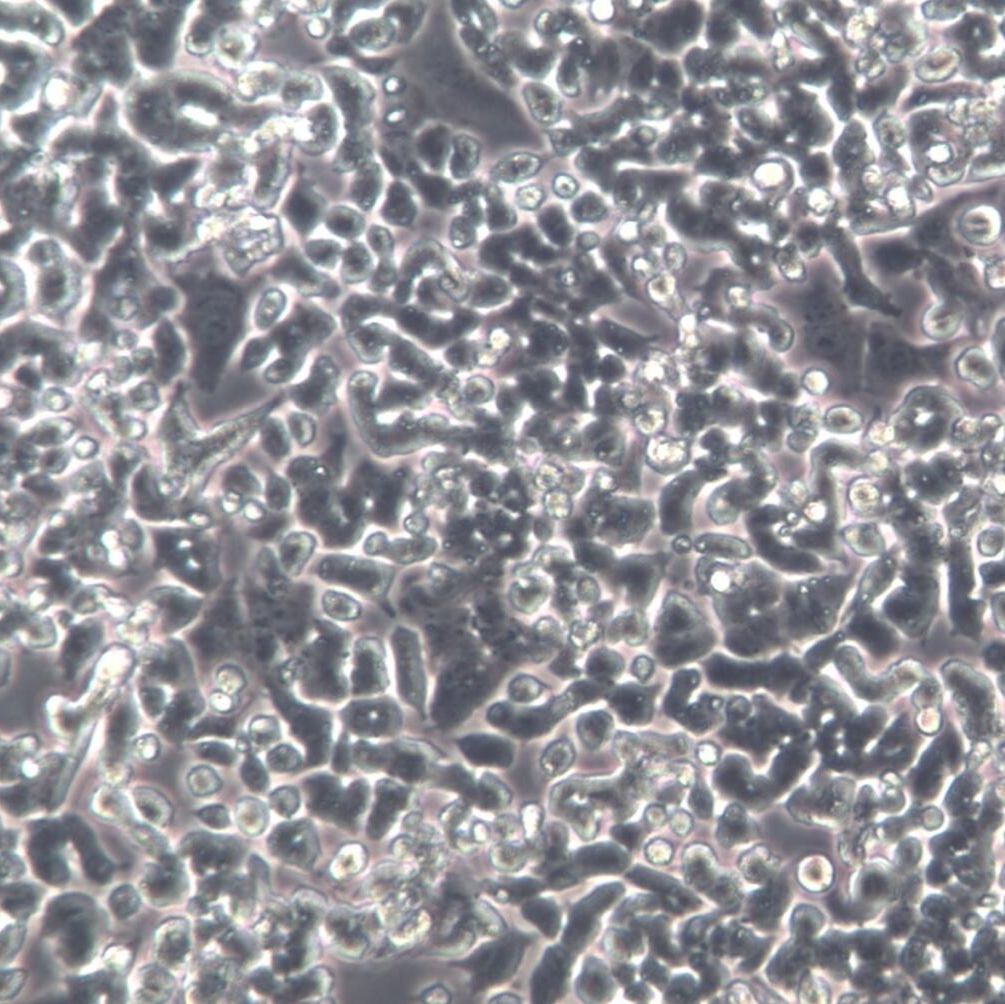

- 细胞形态:

上皮细胞样

- 生长状态:

贴壁生长

FBS.前次换液后,现在还出现了大量悬浮情况,细胞开始聚集成线悬浮于培养基中.按道理说几天就应该传代了啊,请问这是怎么回事呢.分化型和未分化型pc12在生长速度上有差别吗? 丁香园luo_0712的回答: PC12主要有未分化、低分化和高分化三种类型,三种类型的PC12在分裂速度上差异不大,关键在营养要求上。未分化与低分化的PC12一般用DMEM+5%FBS+10%HS;高分化PC12只要用DMEM+10%FBS就可以。你的pc12细胞繁殖速度超慢,平皿的汇合度仅有30%,可能是因为PC12贴壁

丁香园Ginkgokeer的问题:未分化的PC12在什么情况下会使它产生分化,从而成为分化的PC12??是不是NGF有这样的作用?除此以外呢?丁香园sudajyou的观点:pc12 在未分化时贴壁生长,但最好用5%HS, 5%FBS/DMEM培养液,据说PC12在完全没有HS的培养液中贴壁不好。我用的是CORNING的培养皿,PC12贴壁很好。丁香园忘记宝儿兔兔的问题:关于pc12细胞即鼠嗜铬细胞瘤细胞,它是属于神经细胞吗?分化的和未分化的各有什么用途?培养时候大约需要多少天?丁香